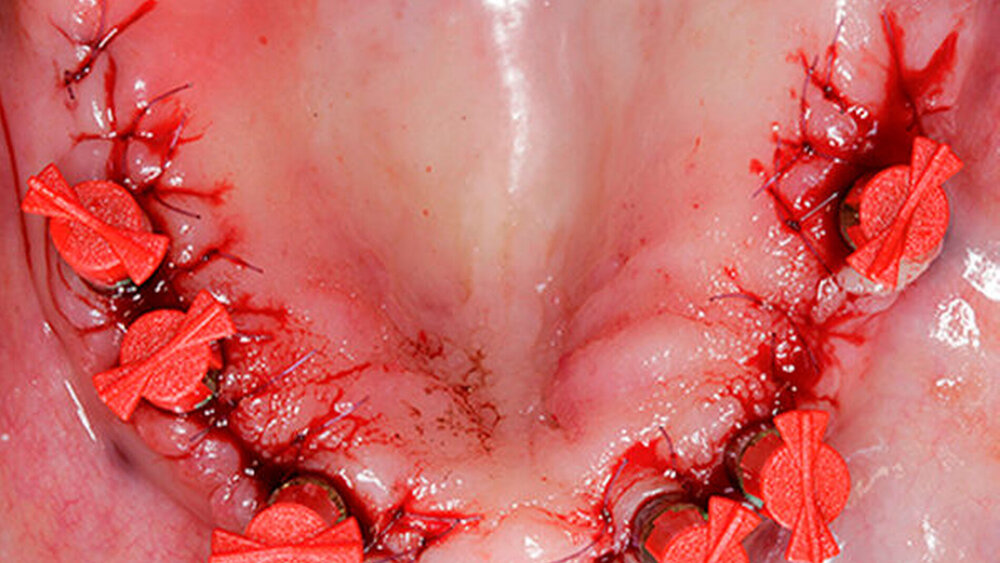

Kommen wir zu Ihrem iSy-Fallbeispiel, bitte beschreiben Sie den Fall genauer.

Gollner:

Eine 67 Jahre alte Patientin stellte sich mit dem Wunsch einer Oberkiefersanierung in unserer Praxis vor. Ihre Restzähne waren aufgrund von Parodontitis und funktioneller Überlastung nicht mehr erhaltungswürdig. Wir ließen sie bis kurz vor der definitiven Versorgung als strategische Pfeilerzähne für die Interimsprothese in situ.